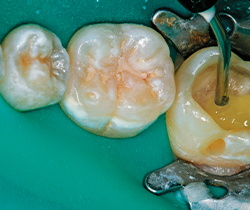

Once the flow layer is placed to idealize depth and opacity, the Tetric EvoCeram Bulk Fill layer shade IVW is placed in one increment, sculpted with OptraSculpt NG (Ivoclar Vivadent) and cured for 10 seconds per surface (Figs. 14-15).

Fig. 14 Fig. 15

The manufacturer recommends five seconds, with the Bluephase 20i in turbo mode, but in the clinical environment it makes sense to increase the cure time depending on access, light proximity and intensity variations. For Class I restorations, the occlusal surface is cured for 10 seconds.